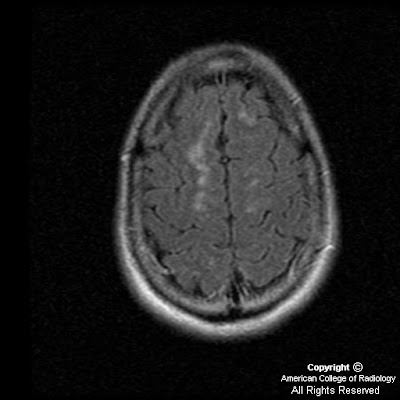

Figure 8: Gradient echo image demonstrates areas of increased magnetic susceptibility in the right thalamus and right frontal white matter consistent with small areas of hemorrhage which were not identified on the CT images.